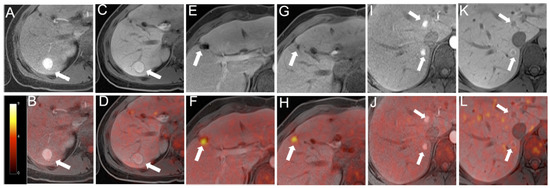

5.3. PET/CT & PET/MRI

- Nensa, F.; Beiderwellen, K.; Heusch, P.; Wetter, A. Clinical applications of PET/MRI: Current status and future perspectives. Diagn. Interv. Radiol. 2014, 20, 438–447. [Google Scholar] [CrossRef] [PubMed]

- Reiner, C.S.; Stolzmann, P.; Husmann, L.; Burger, I.A.; Hüllner, M.W.; Schaefer, N.G.; Schneider, P.M.; von Schulthess, G.K.; Veit-Haibach, P. Protocol requirements and diagnostic value of PET/MR imaging for liver metastasis detection. Eur. J. Nucl. Med. Mol. Imaging 2014, 41, 649–658. [Google Scholar] [CrossRef]

- Kirchner, J.; Sawicki, L.M.; Deuschl, C.; Grüneisen, J.; Beiderwellen, K.; Lauenstein, T.C.; Herrmann, K.; Forsting, M.; Heusch, P.; Umutlu, L. 18 F-FDG PET/MR imaging in patients with suspected liver lesions: Value of liver-specific contrast agent Gadobenate dimeglumine. PLoS ONE 2017, 12. [Google Scholar] [CrossRef] [PubMed]